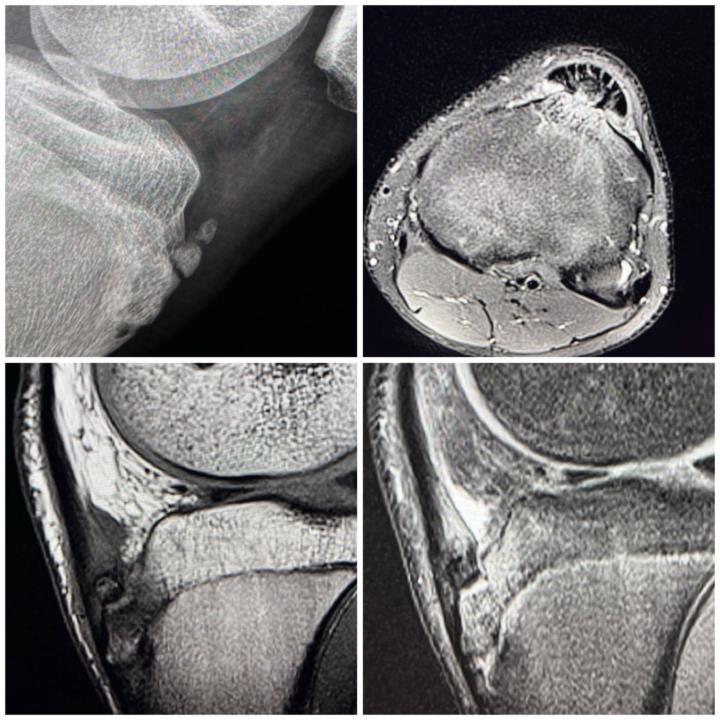

Large Ganglion Cyst of the Flexor Hallucis Longus (FHL) Tendon

🧠 Teaching Case: Large Ganglion Cyst of the Flexor Hallucis Longus (FHL) Tendon with Tenosynovitis on MRI 📌 Clinical Context: A 60-year-old patient presents with pain along the foot. No history of acute trauma. Pain is exacerbated by plantarflexion, especially during activities 📸 MRI Findings: 👉 Sagittal and axial T2-weighted fat-saturated images reveal: A multiloculated, well-defined hyperintense cystic lesion(Blue circle) along the course of the FHL tendon, centered in the forefoot and mid foot region Tenosynovitis: Surrounding high signal fluid within the tendon sheath with mild tendon sheath thickening.(Red arrow) The FHL tendon is intact but slightly flattened within the tunnel, indicating mass effect from the cyst. 🧬 Diagnosis: 🔹 Ganglion cyst of the flexor hallucis longus tendon sheath 🔹 Associated tenosynovitis 🧠 Pearls for Practice: ✅ Ganglion cysts are benign mucin-filled synovial cysts, often arising from joint capsules or tendon sheaths. In the ankle, FHL is a common site due to repetitive motion and mechanical stress. ✅ Tenosynovitis may be reactive or secondary to chronic friction from the cyst. In athletes and dancers, FHL involvement is especially common due to overuse. ✅ MRI is the modality of choice: T1: Hypointense T2/STIR: Hyperintense, well-circumscribed Look for communication with joint or tendon sheath ✅ Clinical Correlation: Symptoms may mimic tarsal tunnel syndrome or posterior ankle impingement. 🩺 Management: Conservative: NSAIDs, rest, activity modification Interventional: Ultrasound-guided aspiration Surgical: Excision if symptomatic or recurrent